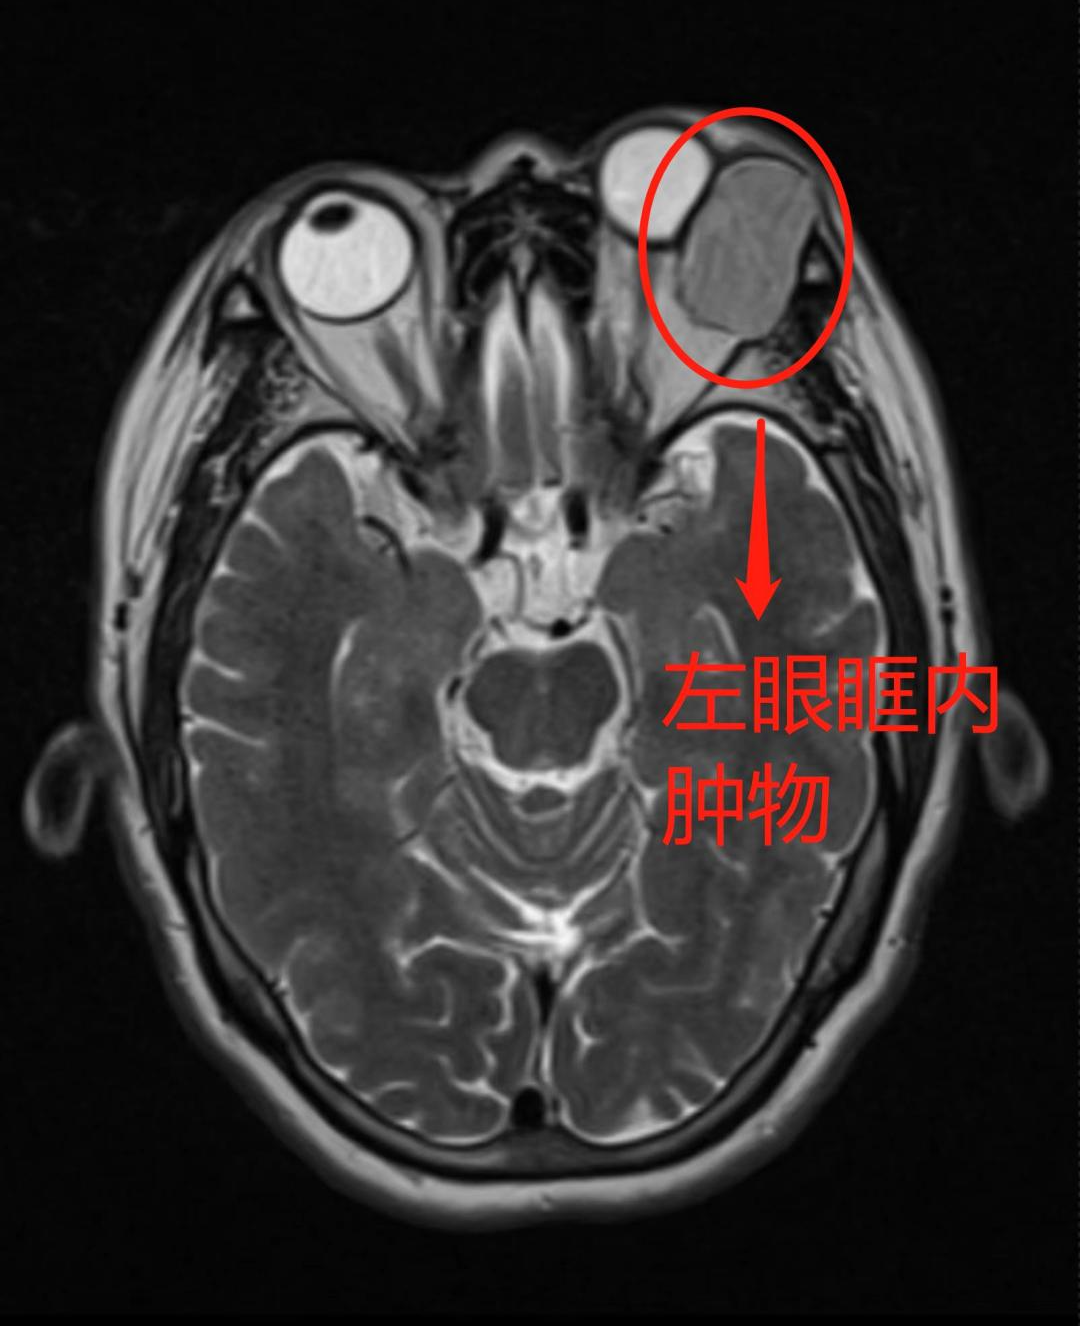

接诊的覃陆路医师给李女士做了详细的眼科检查,眼眶 CT 检查提示为左眼眶内肿物。并且肿物非常大,眼球也因挤压导致移位,肿物还压迫眶骨导致部分骨质吸收。针对这样的情况,覃医师立即建议李女士尽快进行手术切除肿物,以免对眼睛产生更严重的影响。

张九明教授仔细查看李女士的 CT 片后分析:「根据 CT 片显示考虑为泪腺多形性腺瘤可能性大,如此大的肿瘤很可能会发生恶变,应尽快切除!"

在张九明教授与梁鸿刚副主任医师、覃陆路住院医师密切配合、协作下,成功完成这台眼眶肿瘤摘除手术,完整从李女士左眼眼眶中取出约 30 mm 不规则肿物,病理检查报告为左眼泪腺多形性腺瘤。